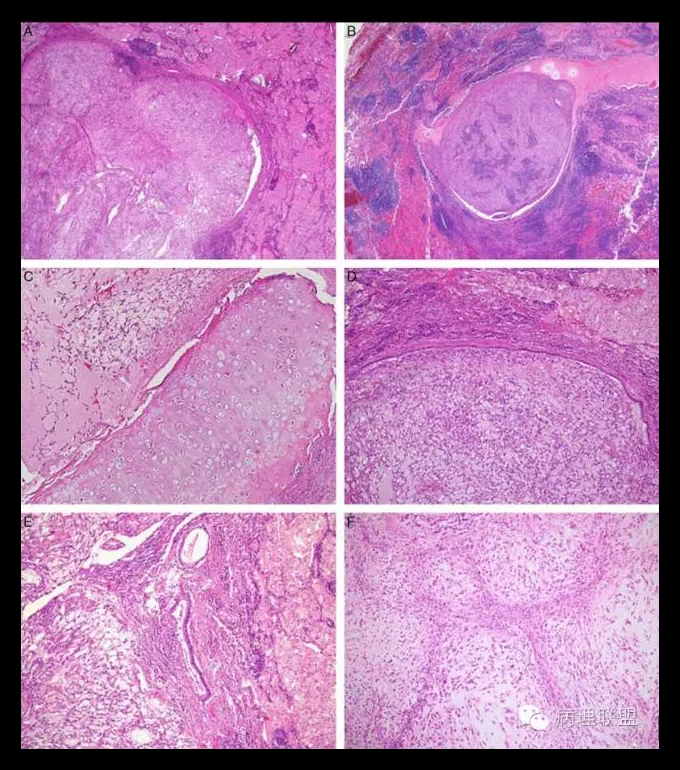

肿瘤位于支气管黏膜下,瘤细胞呈短梭形细胞、卵圆形细胞、多边形细胞和星状细胞,弥漫排列或呈条索状排列,间质呈黏液样。瘤细胞显示有一定的异型性,可见核分裂。形态学类似肌上皮肿瘤或骨外粘液性软骨肉瘤。

伴有EWSRl一CREBI融合性基因的肺原发性黏液样肉瘤(primary pulmonary myxoid sarcoma with EWSRl-CREBI fusion)